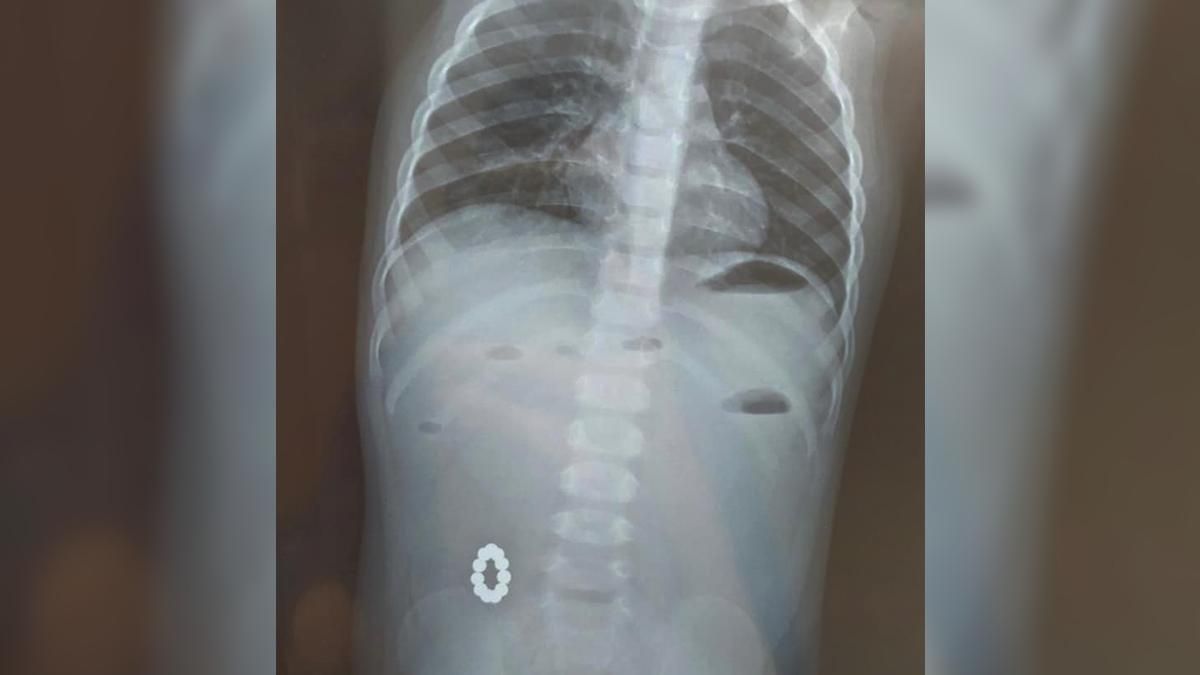

1-летнюю девочку привезли в больницу с подозрением на пищевое отравление. Однако врачи начали ее обследовать и обнаружили круглые магнитики, находившиеся в кишечнике. Они соединились и образовали кольцо.

Магниты, которые врачи достали из малыша / Фото Харьковской областной детской больницы №1

В нашу больницу была доставлена девочка 1 года с подозрением на пищевое отравление, но при совершенной диагностике были обнаружены посторонние тела кишечника!

А именно – магниты, которые между собой соединились и образовали кольцо.